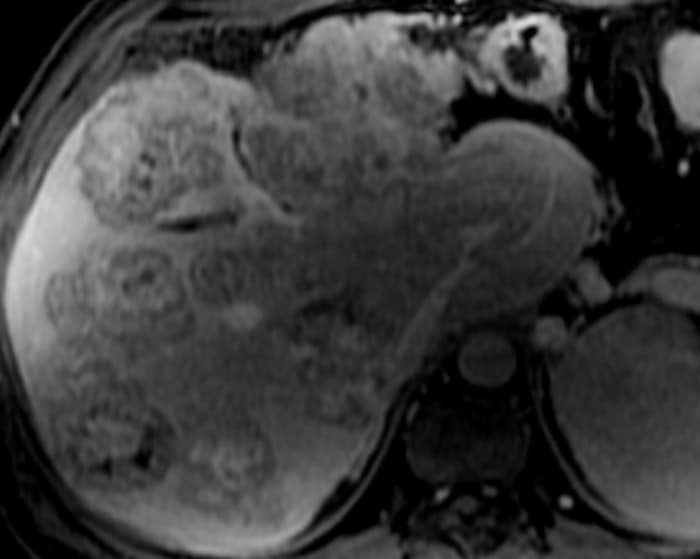

Di căn gan

» Thông tin: Nam giới – 37 tuổi.

» Lâm sàng: Tiền sử K đại tràng.